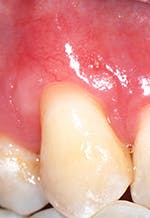

"Recession of the gingiva is becoming a prominent condition in the oral health of many patients and should be treated at its earliest detection," according to A.P. Saadoun in "Current trends in gingival recession coverage - Part I: the tunnel connective tissue graft."5 Saadoun also says the ideal time to correct gingival recession is at a Class I-II, which is less traumatic surgically for the patient, and which achieves predictable regenerative results (see Figures 1, 2).